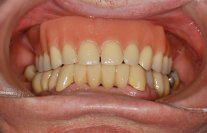

Ein 64 Jahre alter Patient wünscht eine Zahnsanierung (Abb. 1 und 2). Nach intensiver Abklärung des Zustandes der einzelnen Zähne der Restbezahnung sowie der Gesamtsituation (Abb. 3) und der Kostenzusammenstellung wurde folgende Therapie durchgeführt:

Ästhetisch wie auch funktionell entstand ein ausserordentlich schönes Resultat (Abb. 5 und 6).